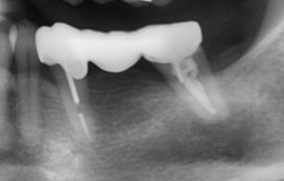

治療後:復原完成,裝上牙橋

治療後X光